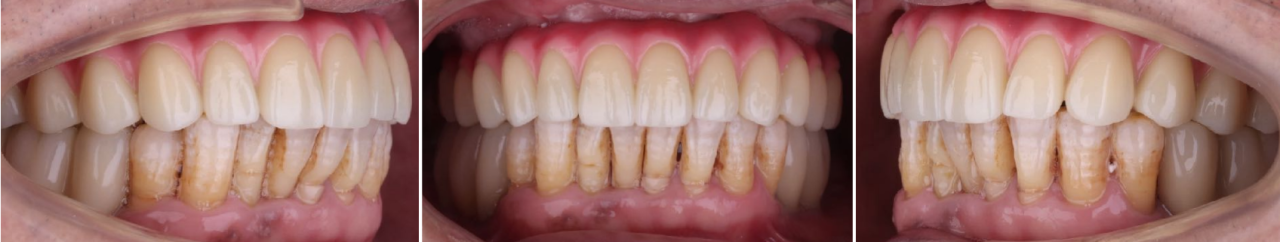

即刻修复5个月后:

边缘骨稳定,上下颌同期行永久修复

永久修复3年随访:

上下颌边缘骨稳定,零骨吸收

通过修复后口内照观察到,美学效果良好,无基台种植体配合性能相关的周围炎。通过医学影像观察到,修复三年后种植体周围无骨吸收,患者非常满意。